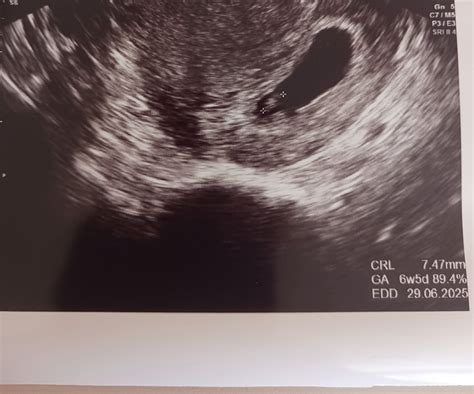

Ultrazvuk v 7. týždni tehotenstva

Prvý ultrazvuk v tomto období môže odhaliť nielen hlavičku, ale aj zreteľné telíčko a končatiny embrya. Chvostík, ktorý sa postupne mení na chrbtovú časť, sa zmenšuje. Jasne viditeľný je žĺtkový vak, cievy rastúcej placenty a pupočná šnúra. Je dôležité poznamenať, že žĺtkový vak je dočasná embryonálna štruktúra zodpovedná za tvorbu prvých krviniek a zárodočných buniek. Jeho prítomnosť je nevyhnutná pre ďalší vývoj.

V prípade, že na ultrazvuku nie je žĺtkový vak viditeľný, môže to znamenať niekoľko vecí. Jednou z možností je, že ovulácia bola posunutá a tehotenstvo je v skutočnosti v skoršej fáze, než sa predpokladalo. V takom prípade by sa žĺtkový vak mal objaviť na nasledujúcej kontrole. Inou, vážnejšou možnosťou, je anembryomola, stav, kedy síce došlo k oplodneniu a rastu gestačného vaku, ale plod sa nevyvinul. V takom prípade je často potrebný lekársky zákrok.